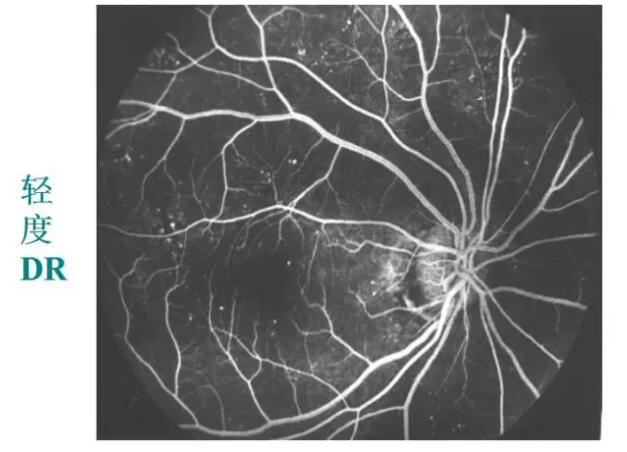

糖网病的眼底表现

微血管瘤

出血斑

渗出

视网膜静脉扩张、动脉变细、小血管闭塞

新生血管

玻璃体积血

牵拉性视网膜脱离

眼底荧光血管造影:更清楚、更敏锐